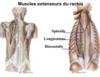

Nommez les catégories de muscles du rachis (3)

- Muscles antérieurs

- Muscles postérieurs

- Muscles respiratoires

Identifiez